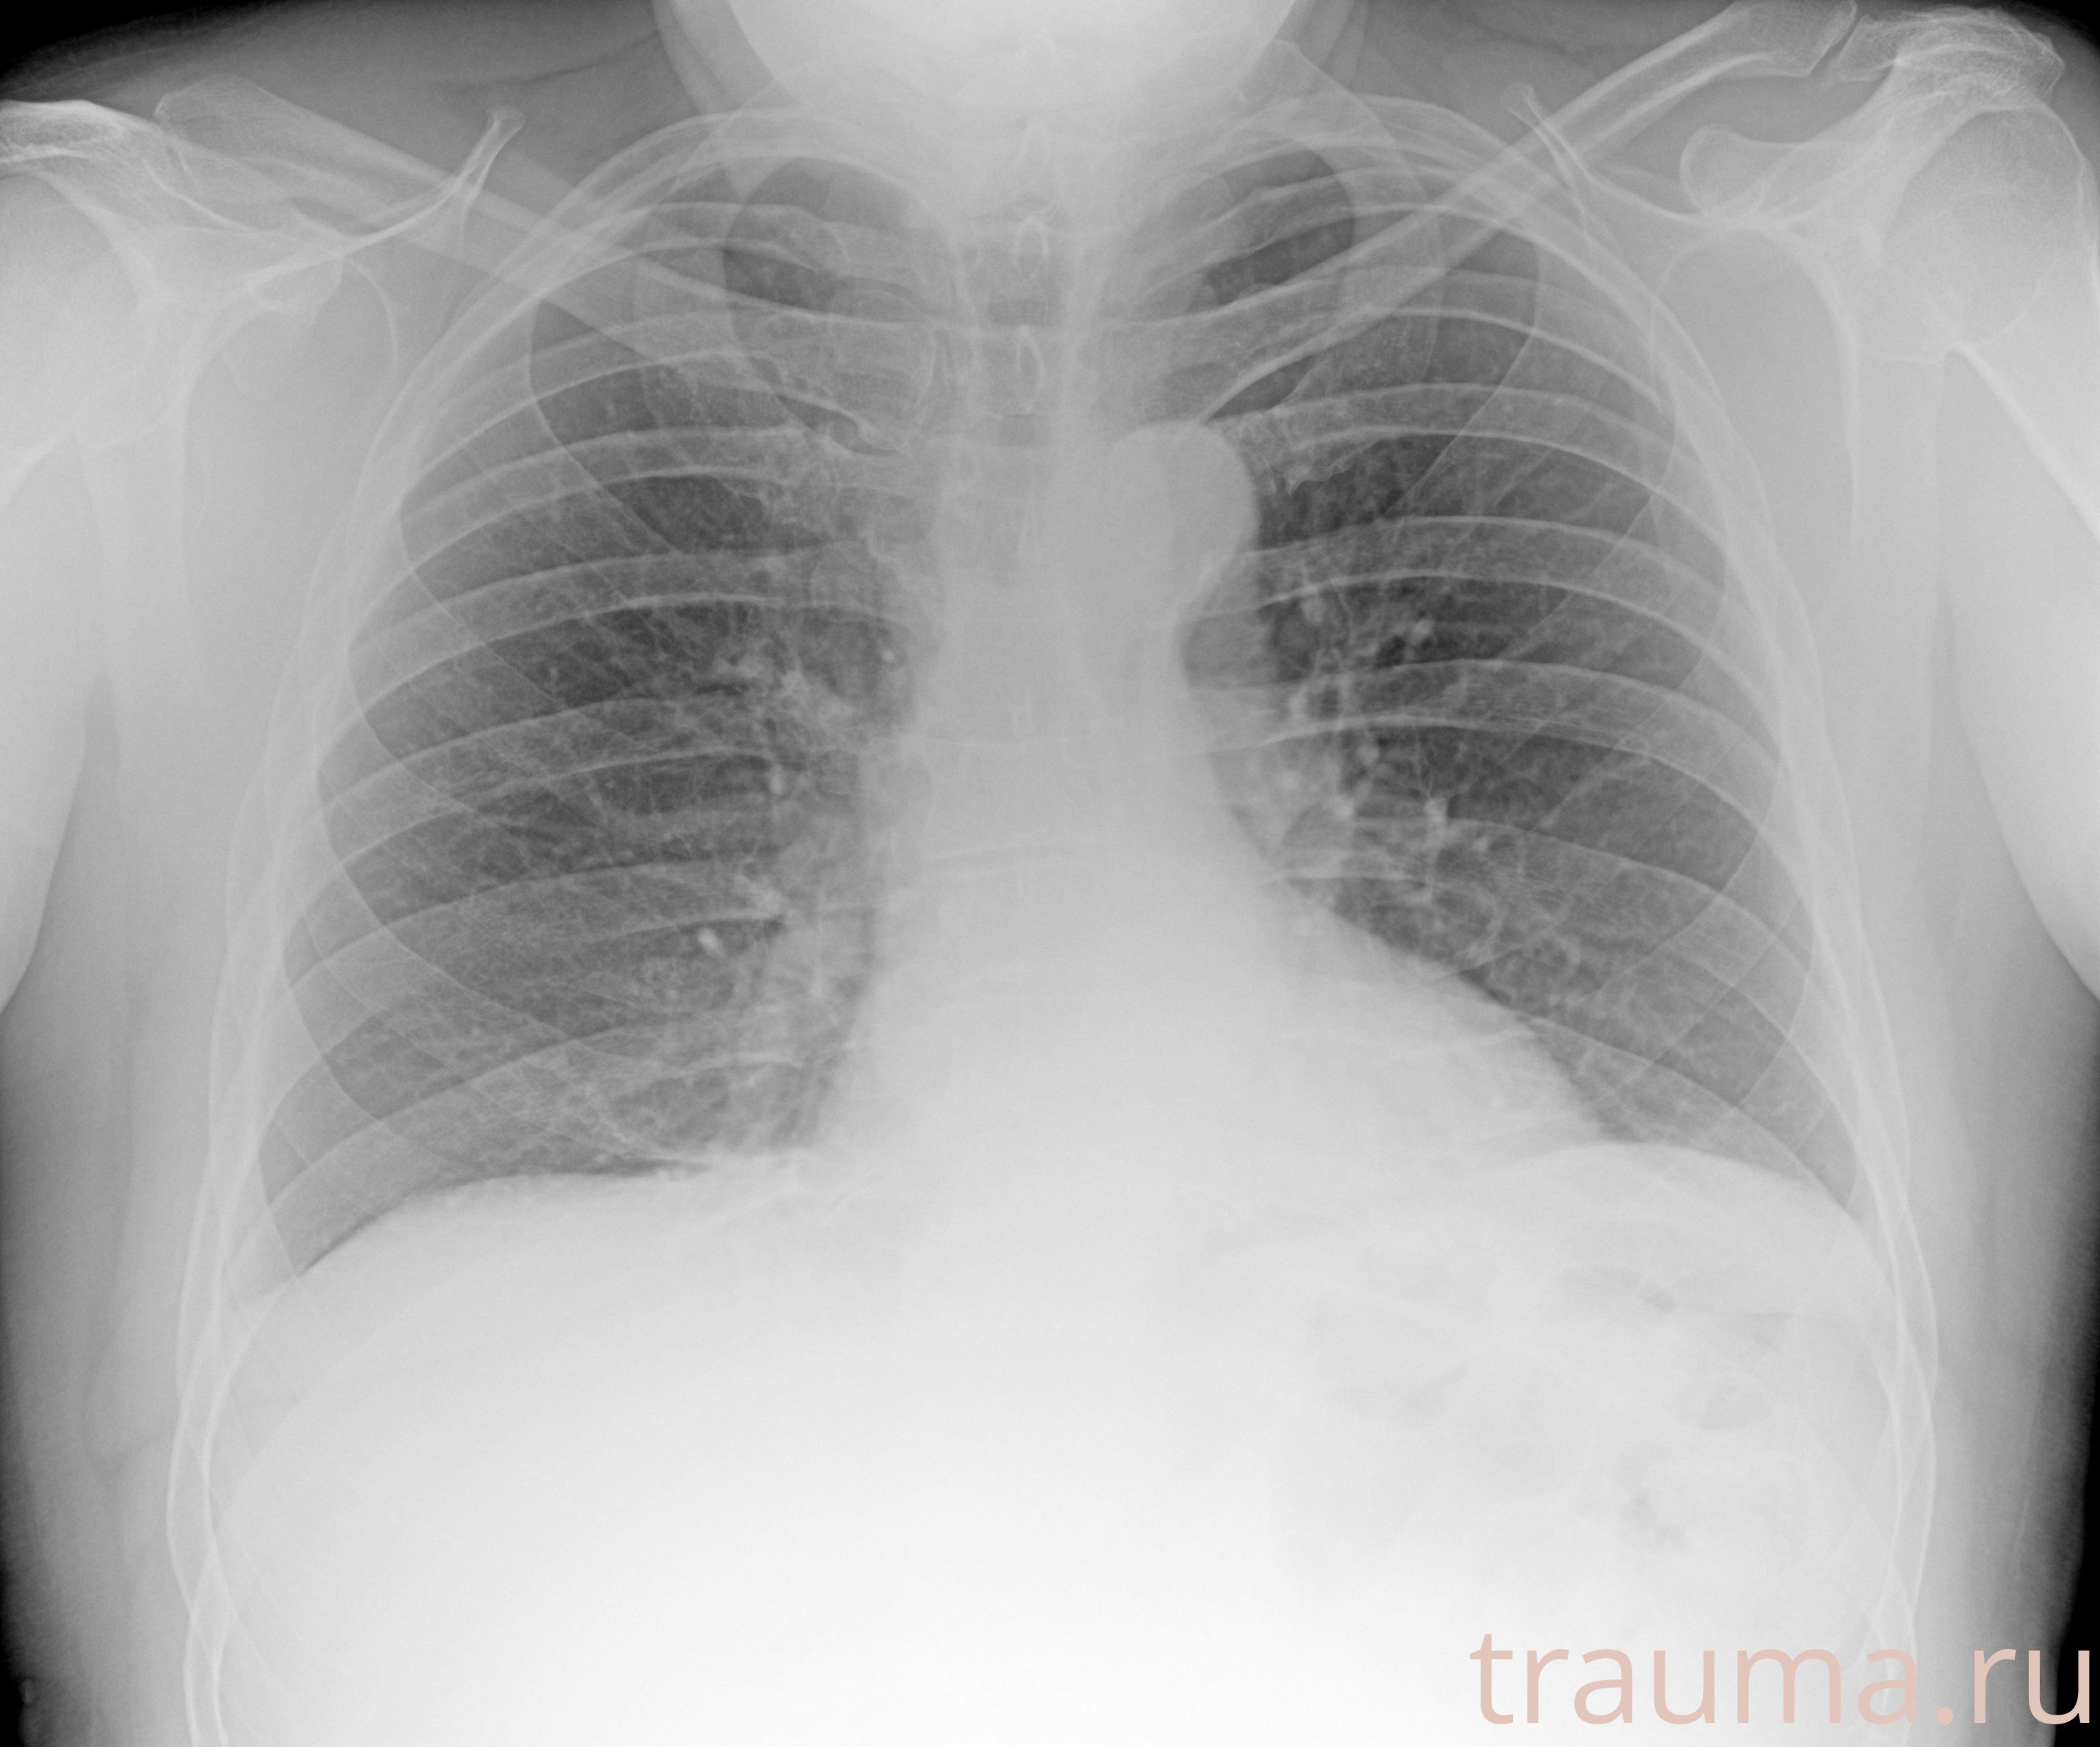

Рентгенограммы

Рентген на дому: по вашему адресу приезжает врач-рентгенолог, травматолог-ортопед с мобильным рентгеновским аппаратом, проводит диагностику травмы или заболевания, делает необходимые рентгенограммы, дает рекомендации по дальнейшему лечению. Получить качественные снимки в домашних условиях возможно благодаря уникальной методике, разработанной МосРентген Центром для института  Склифосовского